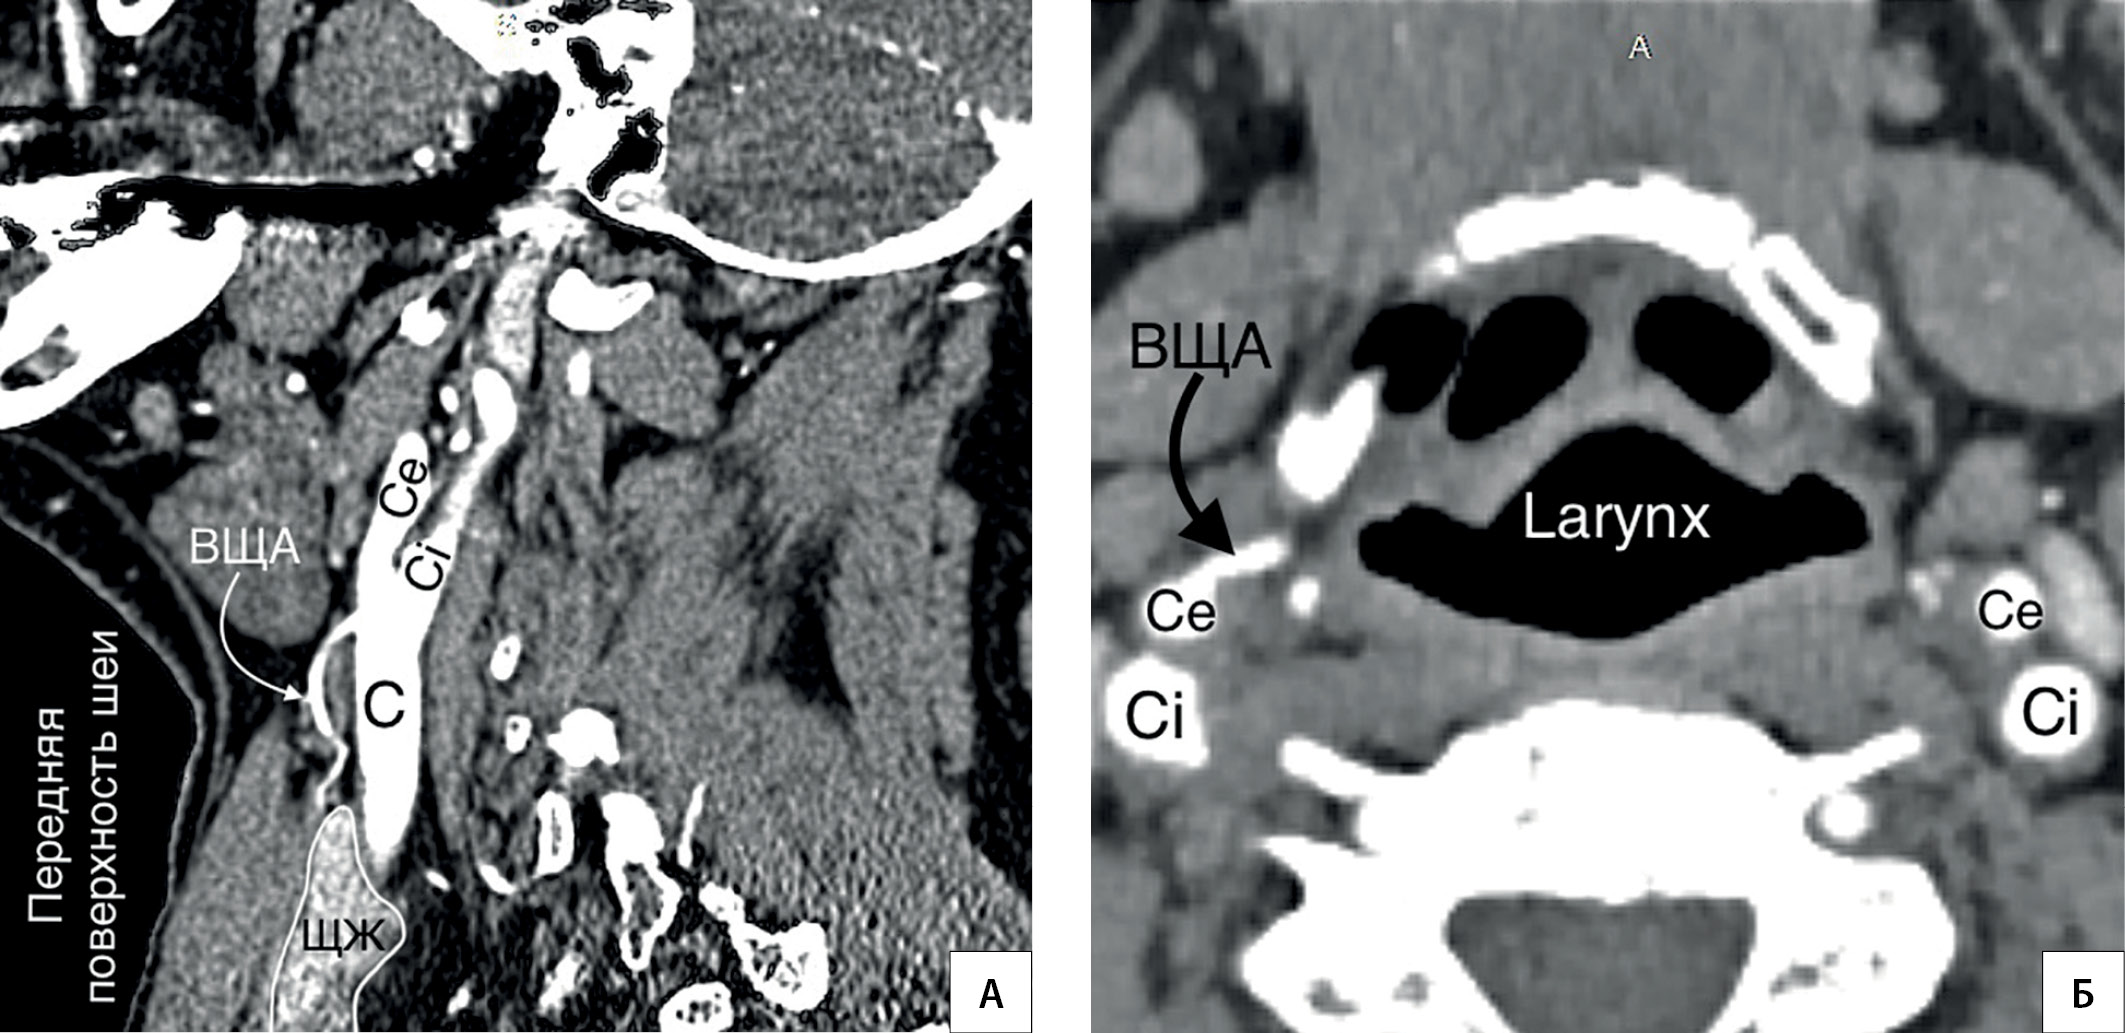

10. Рисунок 10. Источник ВЩА. А — КТ-ангиография (сагиттальный срез). Источником ВЩА является бифуркация общей сонной артерии; Б — КТ-ангиография (горизонтальный срез). ВЩА берет начало от наружной сонной артерии. C — a. carotis communis; Ce — a. carotis externa; Ci — a. carotis interna.

Тема

Тип Исследовательские инструменты

Посмотреть (313KB)

Метаданные ▾